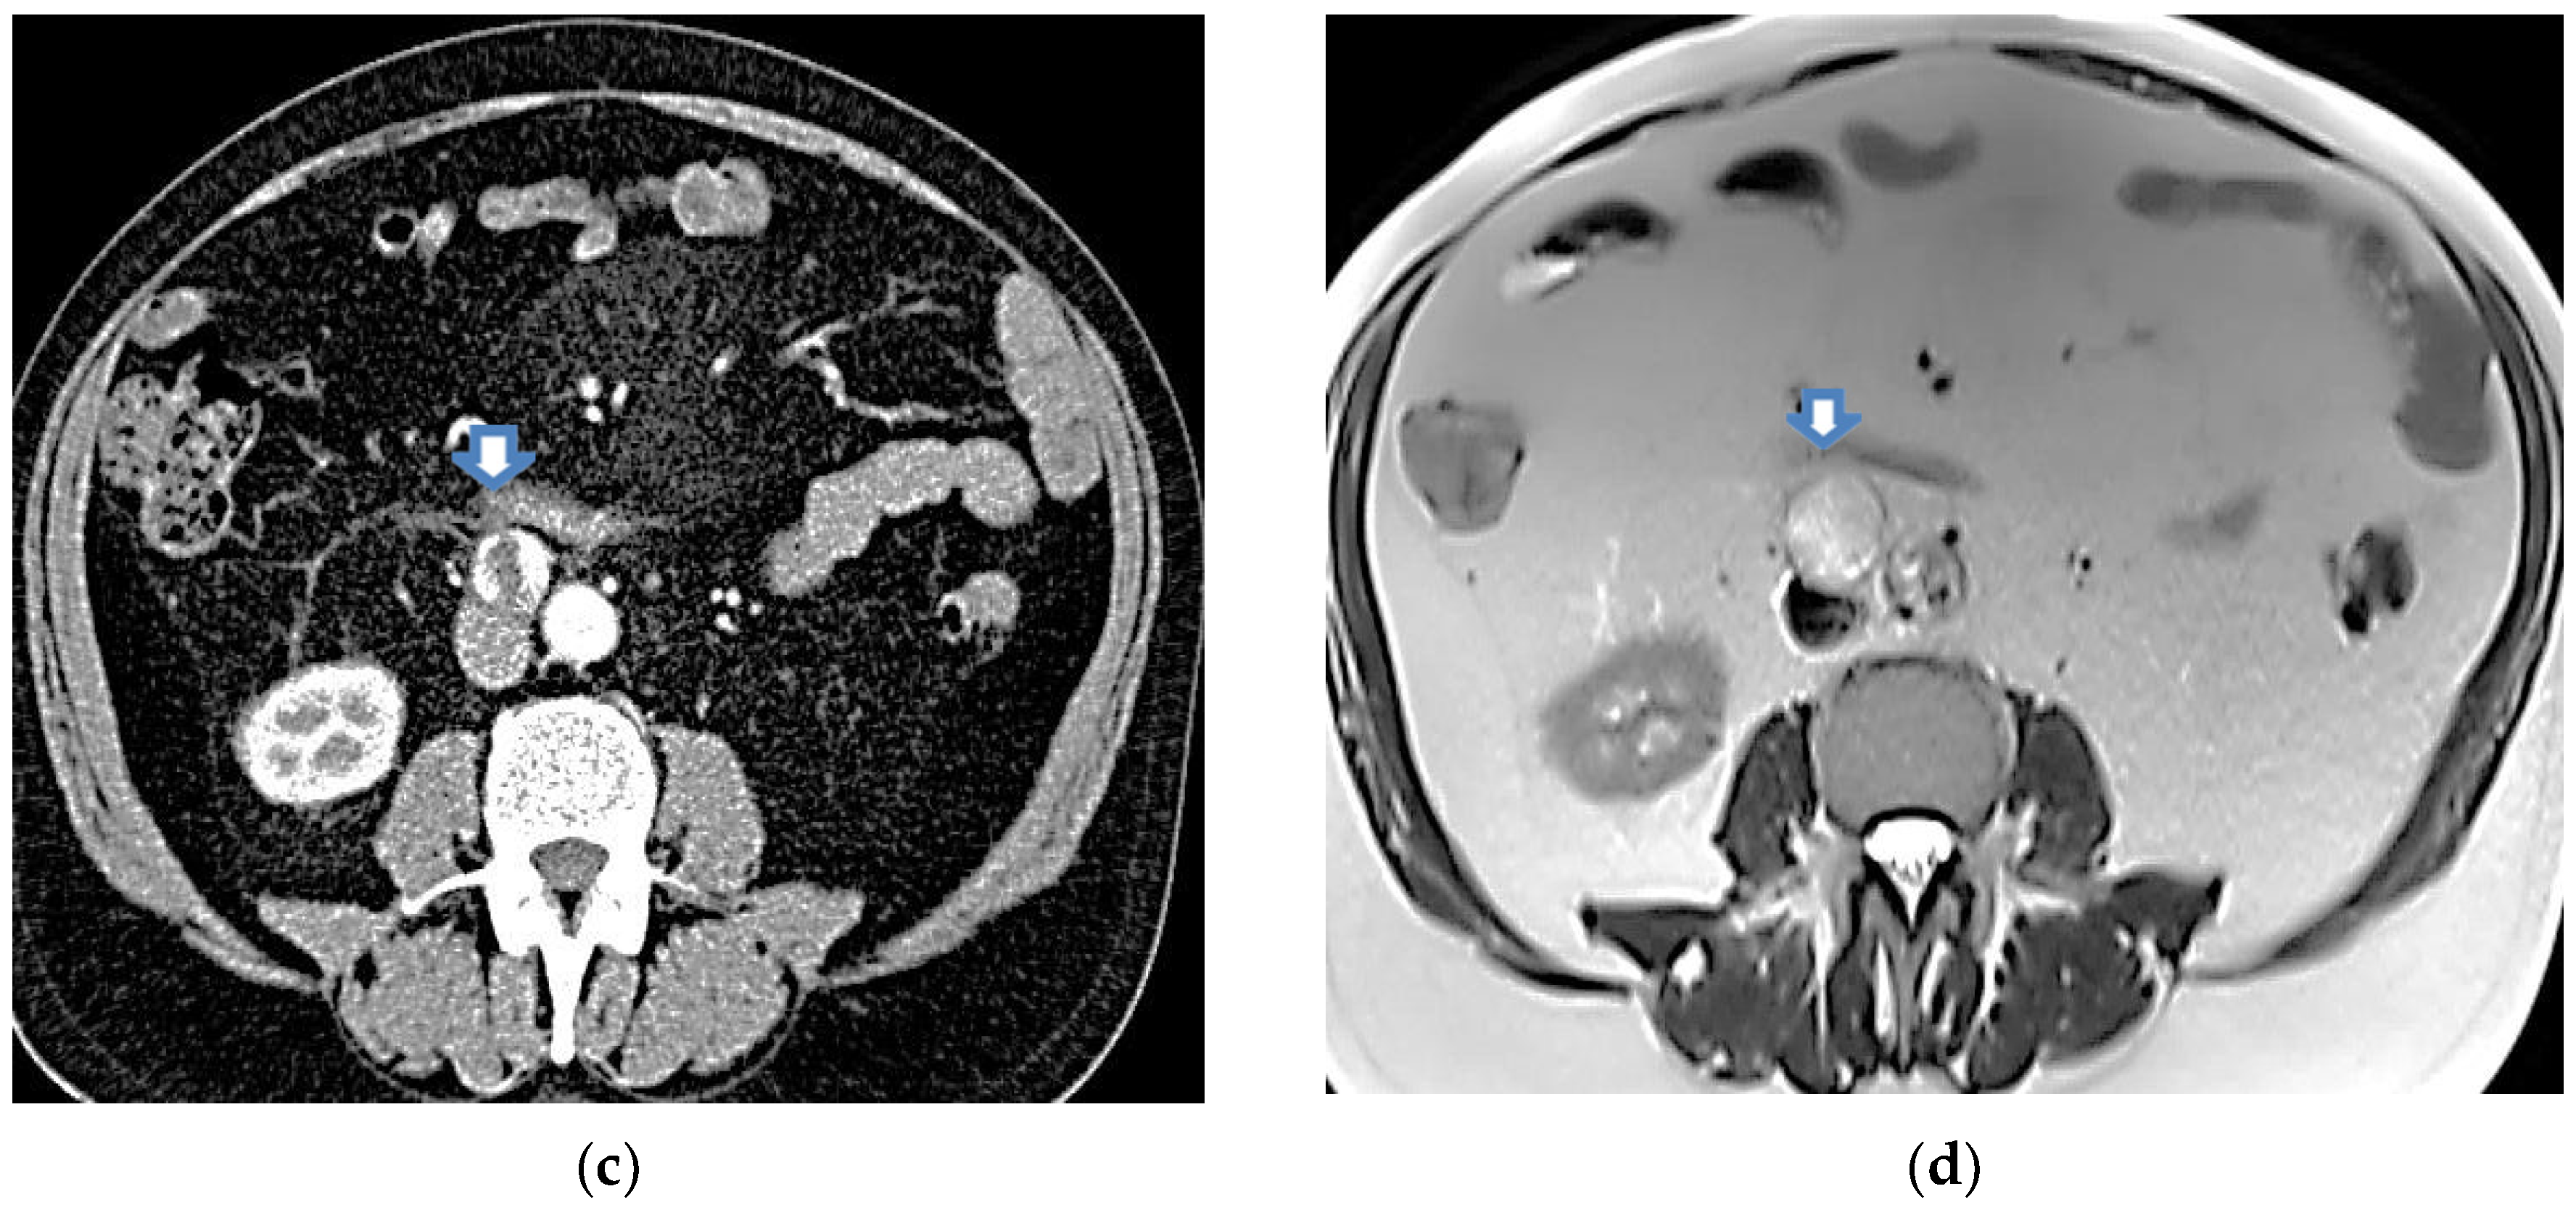

2.3. Imaging Tests